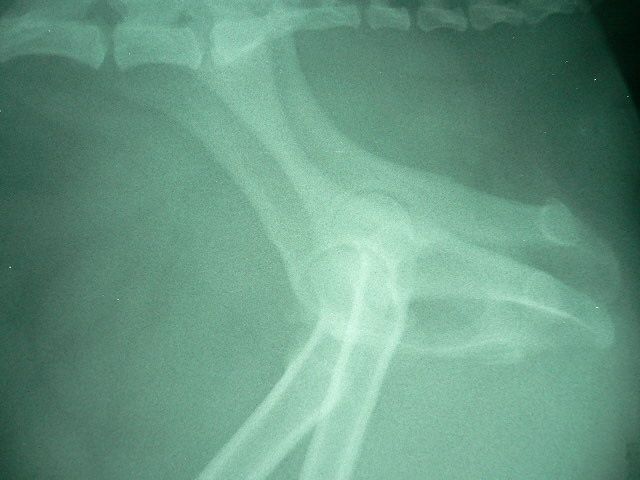

本日、テーピングを取るために鎮静処置を行いました。レントゲン写真で確認を行い、股関節が正常位置にキープされていることが分かり、煩わしかったテーピングを晴れて外すことができました。これから約2週間ほどは、引き綱をつけのリハビリが必要です。今度は、指示を守ってくれるのでしょうか?「あまりはしゃぎすぎると、また外れるョ〜!」